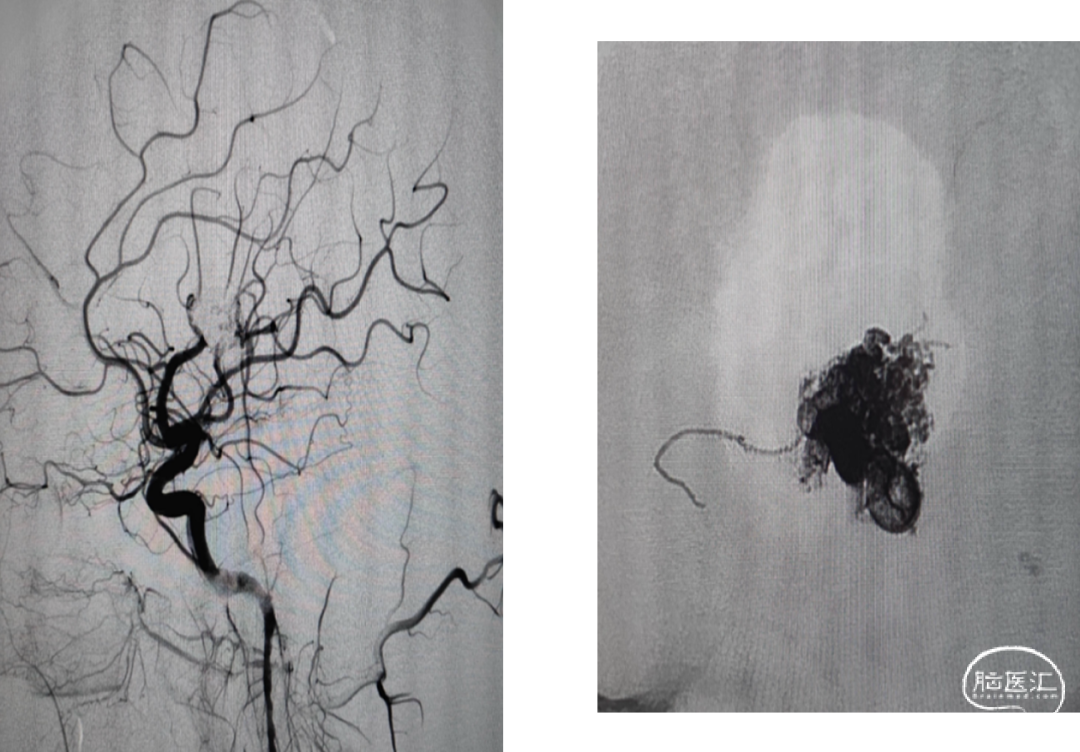

球囊保护静脉入路栓塞:注射onyx34约1ml,onyx18约1.5ml,总时长20min。

术后即刻造影畸形血管团不显影

术后CT复查,少量出血,癫痫发作,继续控压、抗癫痫等治疗